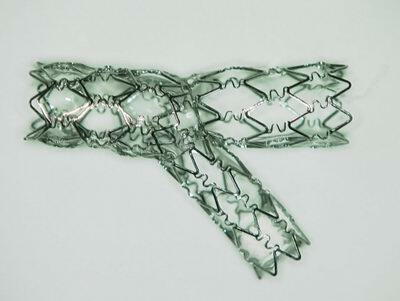

先日、CypherのベースになっているVelocityを使ってYステントの

実験をしてみました。ガイダント社で作成されたポリビニールアル

コール(PVA)製の冠動脈模型の中で4mmと3mmのVelocityを使

ってYステントを施行しました。deployはどちらも16atmで、最終の

In stent-KBTは8atmで行っています。Yステント施行後に熱湯の

中でPVAを溶解し、ステントのみを写真撮影しています。結果は

添付の写真に示すとおりで、従来より指摘されていたとおりに、

本管にくびれができています。closed cell typeのステントの問題

点が明瞭に示されている結果でした。本管側が3mmを超えるよう

な状況下でのCypher-Y stentingにはやはり問題がありそうです。